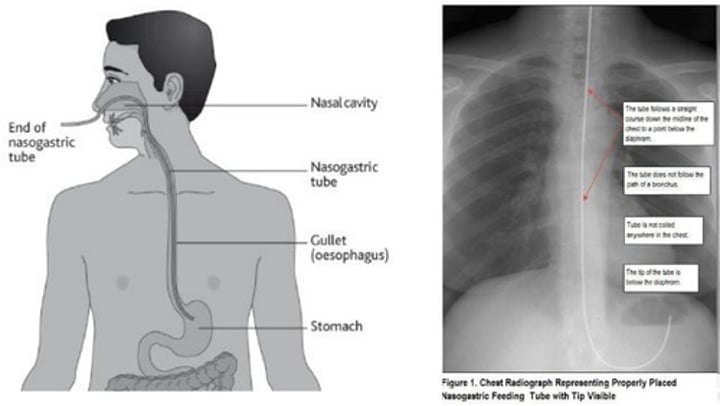

NG tubes

Initial placement checked by X-ray

-Subsequent placement checked by aspirating stomach contents

If patient starts coughing during implementation of NG tube, what should the nurse do?

Remove NG tube and try again!